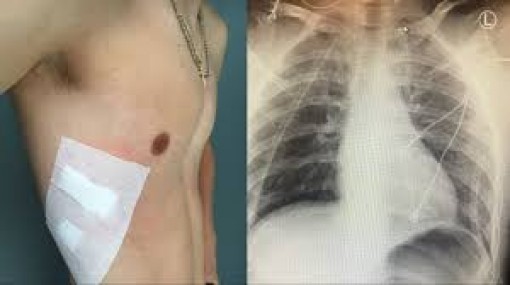

AI chẩn đoán COVID-19 trên phim X-quang đúng và nhanh gấp 10 lần chuyên gia

Đối với nhiều bệnh nhân COVID-19, ảnh chụp X-quang vùng ngực cho ra kết quả khá giống nhau. Theo đó, phổi của họ loang lổ những đốm hoặc mảng mờ vì chứa đầy chất dịch và bị viêm, đặc biệt là các khu vực dọc theo thùy dưới và vùng ngoại vi.